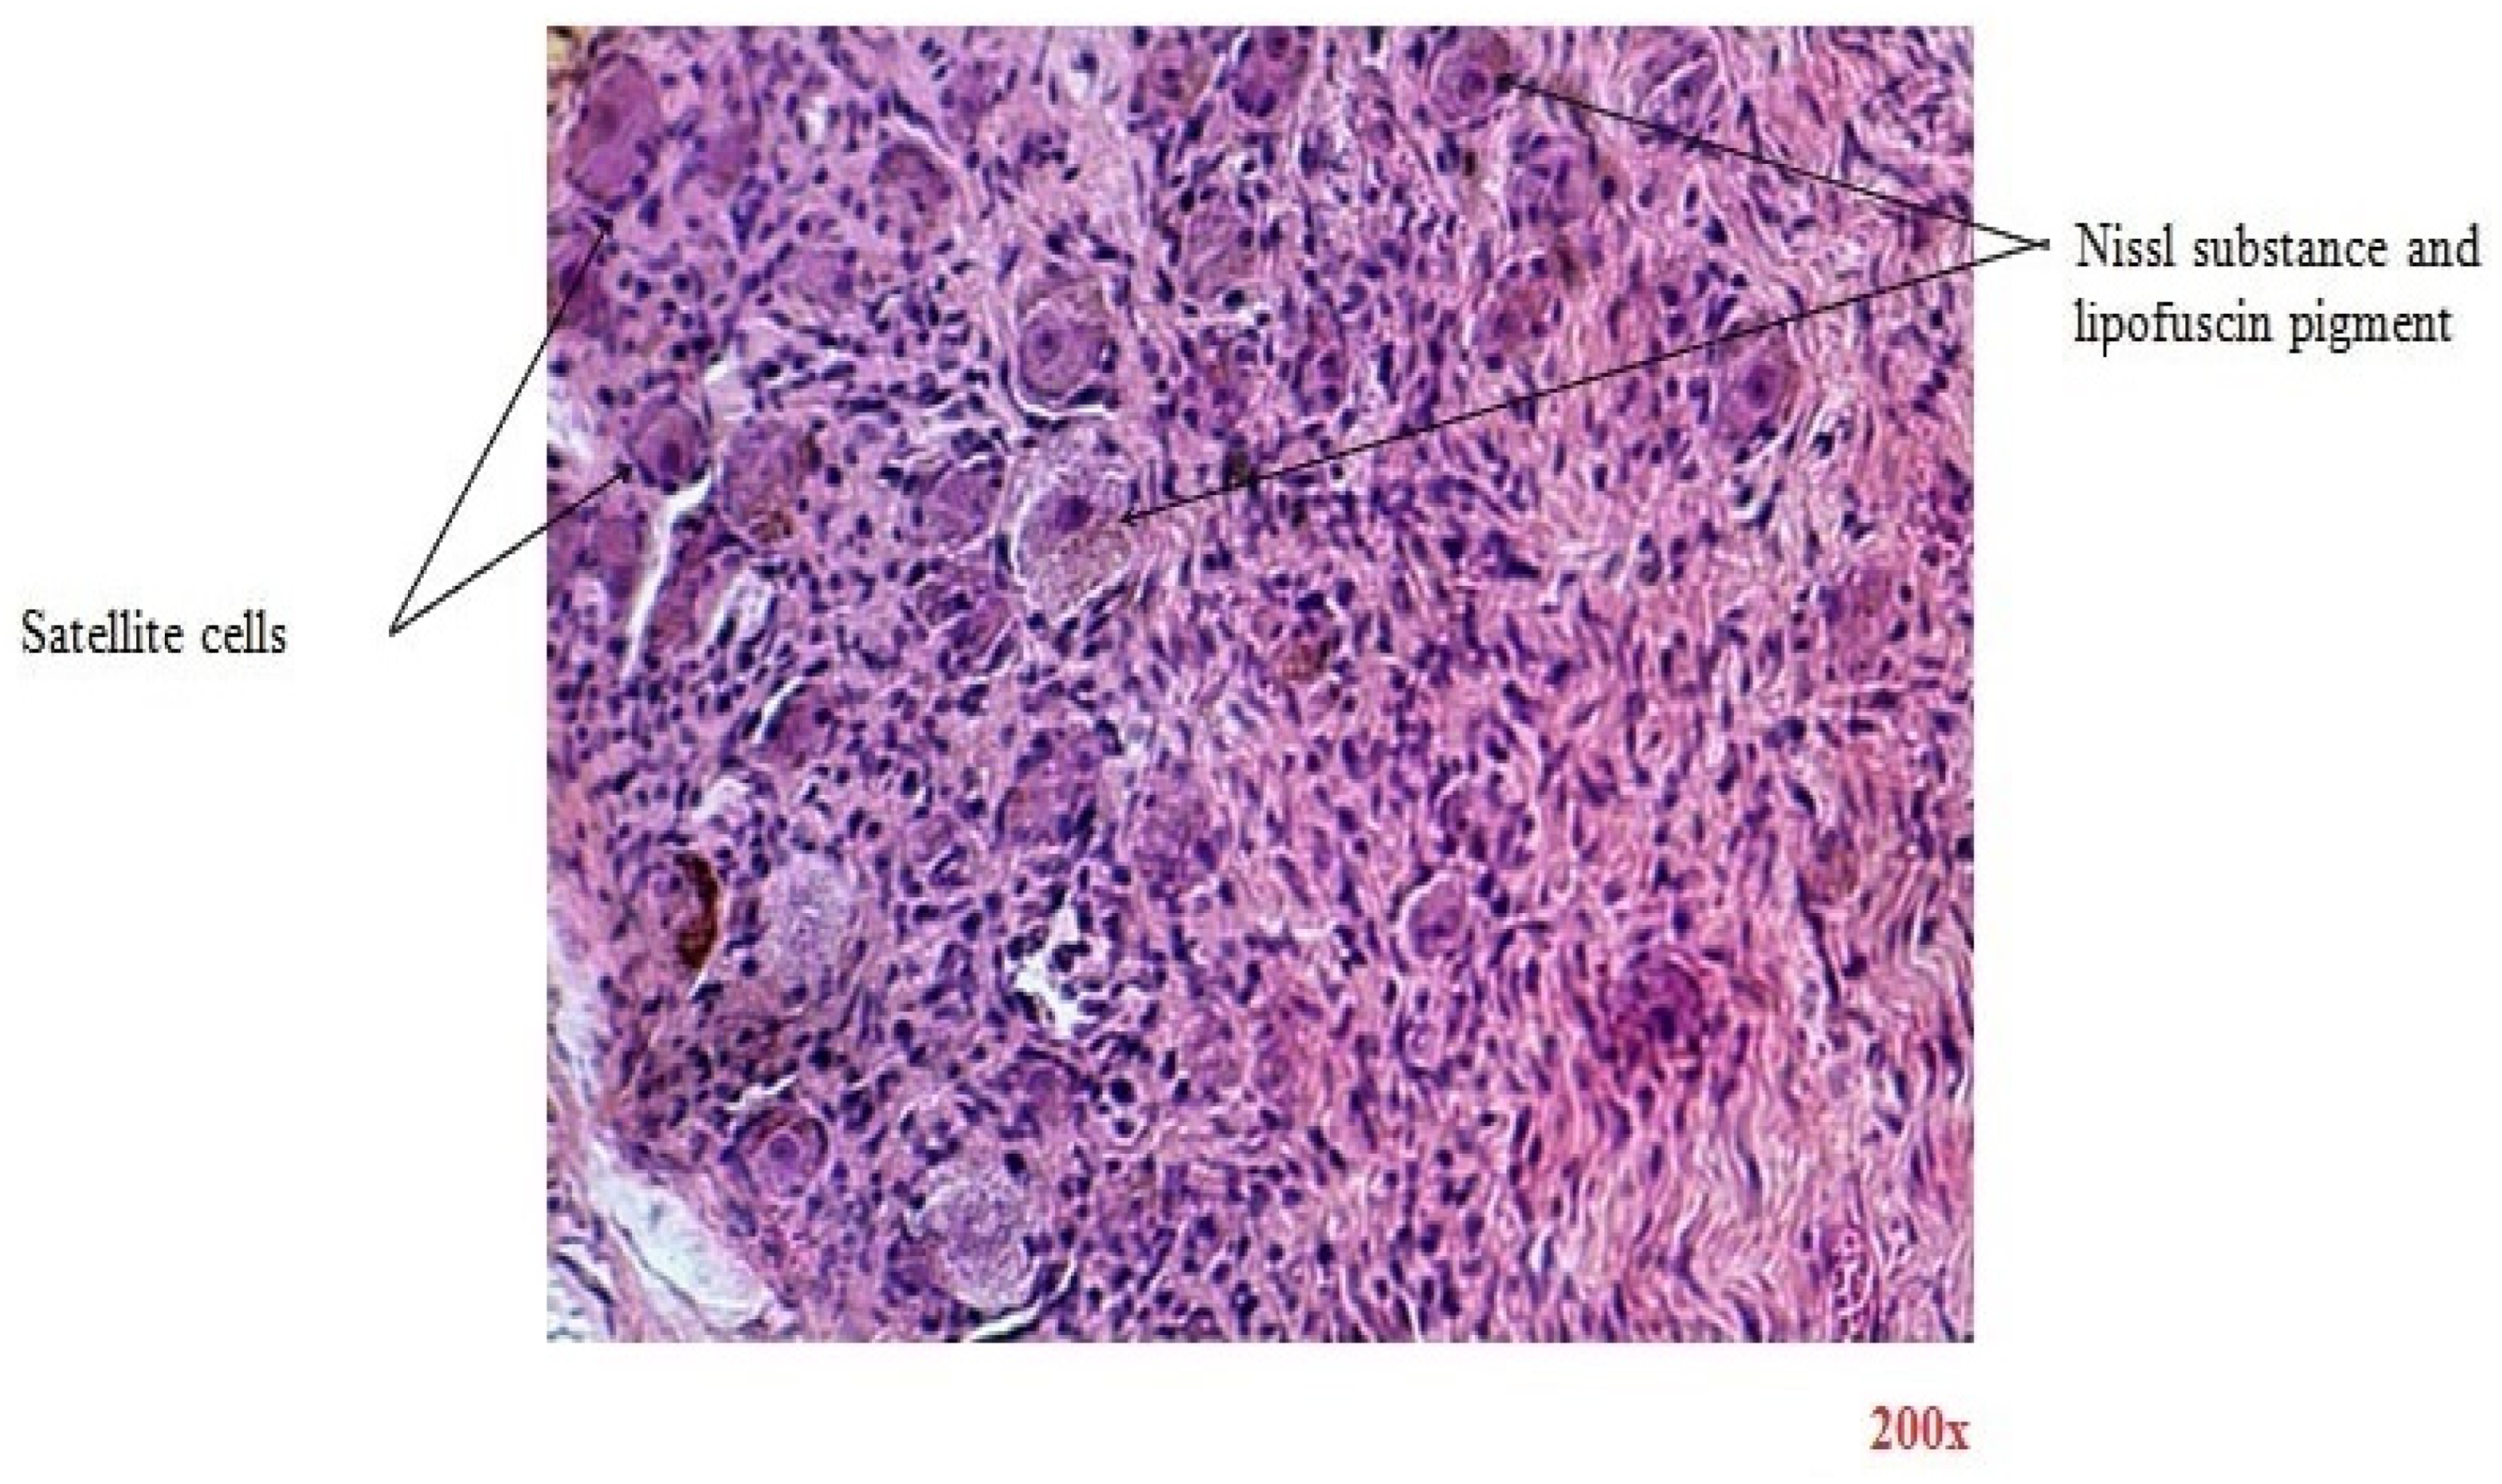

There are similar results in terms of microscopic imaging between the two categories. In Figure 3, the H&E-stained section reveals the ganglion that is encased in fibrous tissue sheaths that surround the components of the nervous structures. Ganglion cells are large nerve cell bodies with large excentric nuclei and prominent nucleoli. Their cytoplasm contains abundant basophilic Nissl substance, which represents the granular endoplasmic reticulum and ribosomes. Lipofuscin yellow-brown pigment granules can also be found in some nerve cell bodies. At the periphery of nerve cell bodies, small round satellite cells (glial cells) are found. Nerve fibers are defined by non-myelinated and myelinated axons of different diameters seen in the cross-section. Schwann cells are glial cells responsible for insulating axons in the peripheral nervous system by forming the myelin sheath. This sheath, which appears pink, encases myelinated axons, facilitating efficient nerve signal transmission. Interspersed within the nervous tissue are fibroblasts, which contribute to structural support and provide a context for the spatial organization of nerve cells.

Figure 3. Transverse section through celiac ganglion (H&E-stained section, magnification 200×).